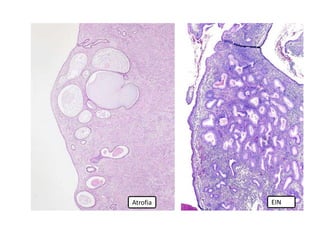

Hiperplasia simples /

Neoplasia intraepitelial endometrial

Hiperplasia simples

EINAtrofia

EIN (hematoxilina-eosina) PTEN (imunoistoquímica)

Phosphatase and tensin homolog (PTEN)